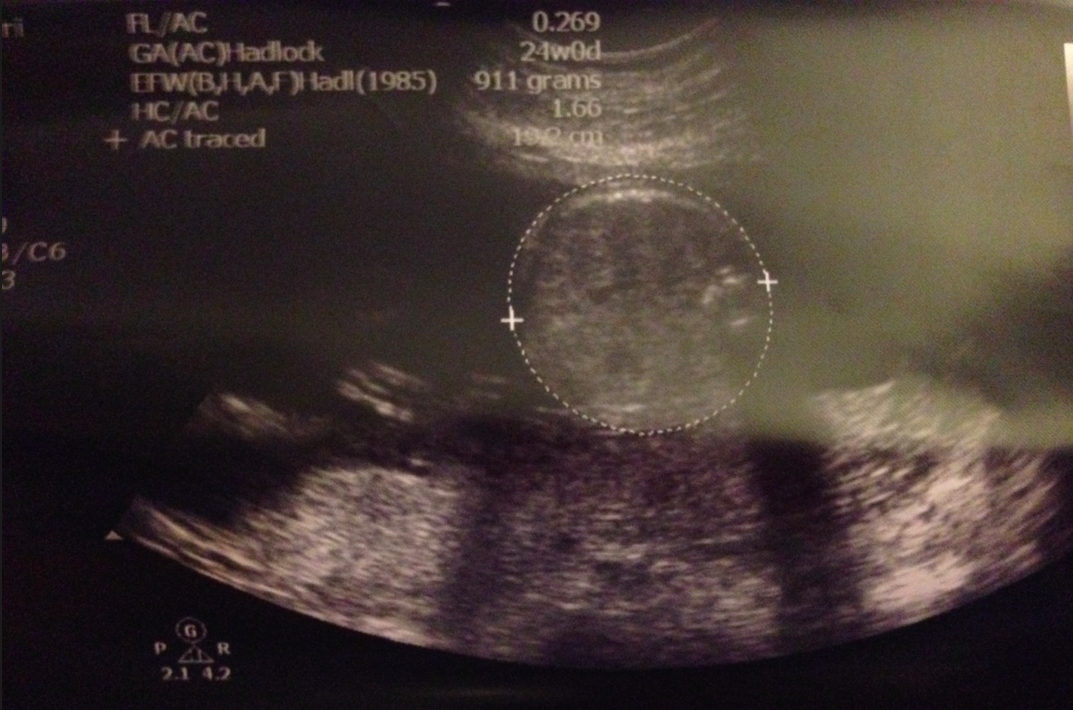

肚腩⋯erhhh?24週size?﹗其實,S醫生話啲parameters係呢啲週數如果正負一星期都屬於完全正常,其實唔駛擔心,不過嘛,得啖笑囉~自從我肚子越來越大之後,day個肚腩都改咗個名叫做邱肚腩,莫非BB呱都有邱小肚腩?﹗:p記得乖乖地,唔好繼續放肆亂咁長肉啦,按步就班,跟時間表生長就最好了﹗知唔知道?

S醫生仲睇咗好多其他部位,有啲睇番相相唔記得咗係乜就唔寫了,記得學咗新嘢,不嬲我都知道要用超聲波做dating的話,即是用超聲波尺寸計番胎兒週數,都係1st trimester時最準,2nd trimester都有多少資訊,再遲就冇意思了,原來量度BB嘅小腦尺寸的話同週數correlate得好好㗎﹗幾多mm就係幾多週,BB呱當然跟番住係23mm啦﹗我哋又數下手指仔腳指仔,係螢光幕上,BB呱繼續「烏蠅手」,郁郁郁郁郁,S醫生都好難捉住佢呢﹗heehee~